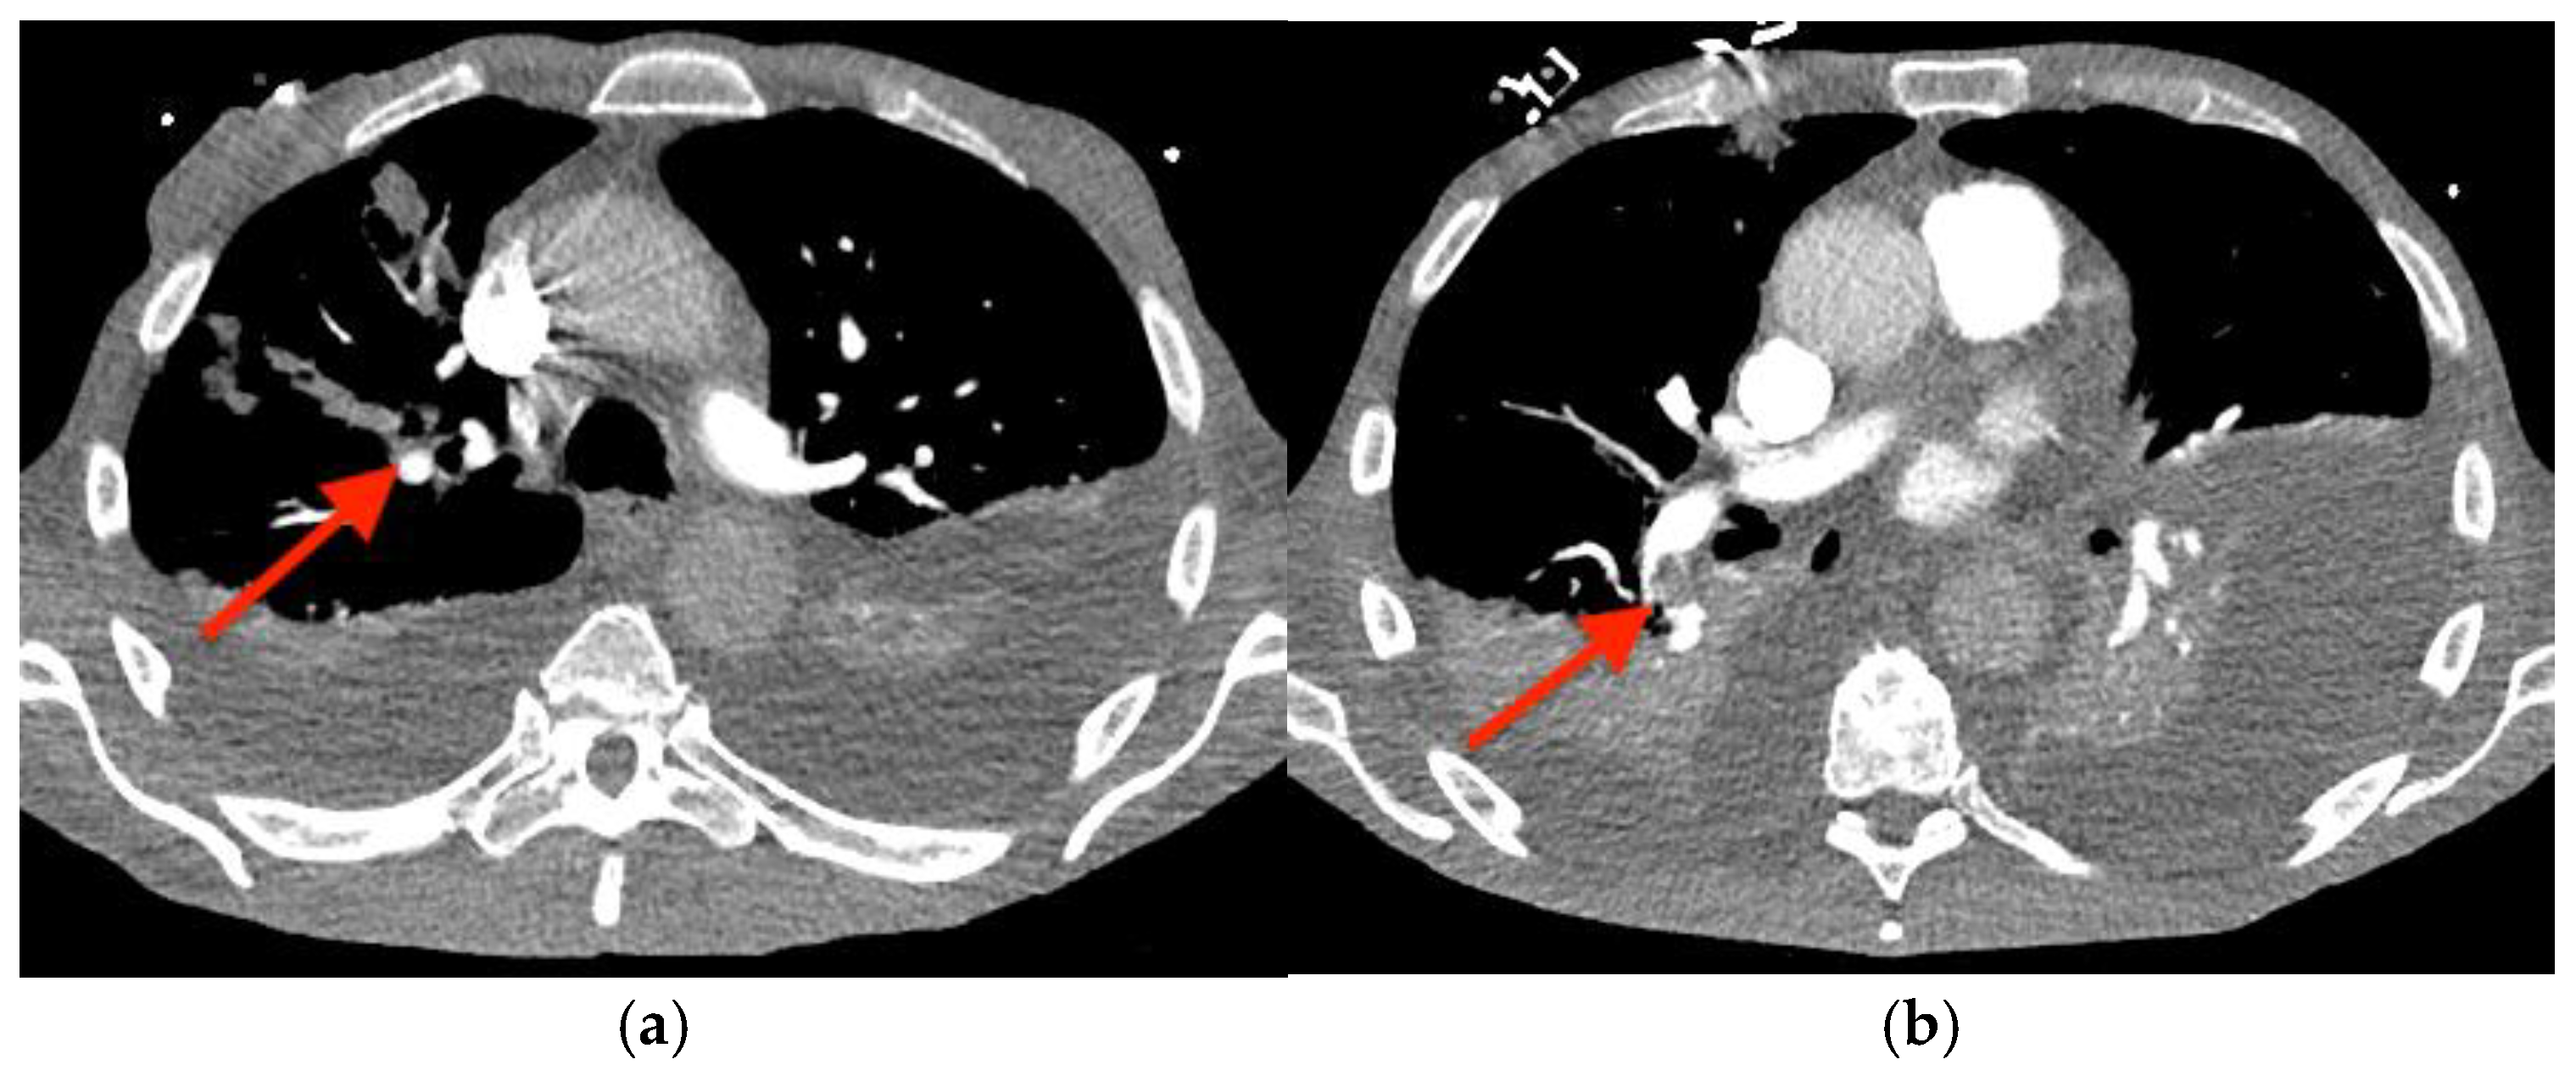

Before outpatient surgery could be performed, he was readmitted to the hospital with dyspnea, bradycardia, and hypotension. A computed tomography angiogram of the chest revealed right upper and lower lobe pulmonary emboli (Figure 5), and intravenous heparin was started. A transesophageal echocardiogram showed growth of the TV vegetation to 4.0 × 3.0 cm (Videos S5 and S6). A transthoracic echocardiogram showed newly reduced left ventricular systolic function (ejection fraction of 35–40%); a dilated, hypokinetic right ventricle; and the absence of an intracardiac shunt. (For a video of the transesophageal echocardiogram with cardiologist commentary, see Video S7.)

Figure 5. Computed tomography angiogram of the chest showing pulmonary emboli (red arrows) in: (a) the right upper lobe and (b) the right lower lobe.